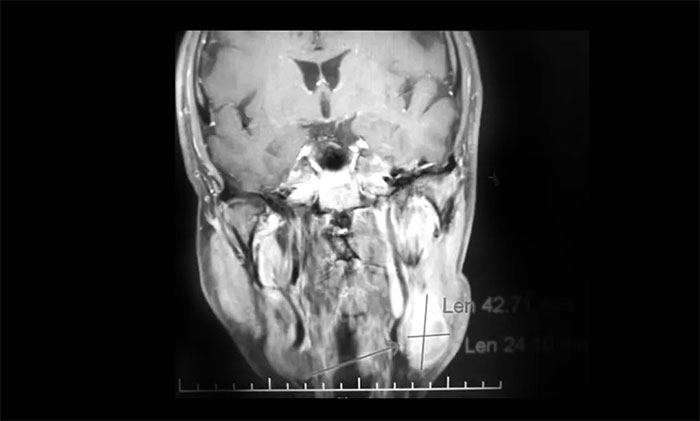

經(jīng)MDT多學(xué)科會診評估,制定以放療為主的同步放化療方案。治療后復(fù)查MRI,患者左側(cè)鼻咽部實(shí)性占位較前治療明顯減小;原左側(cè)下頜腺區(qū)、咽旁腫大淋巴結(jié)已基本吸收好轉(zhuǎn),左頸部腫大淋巴結(jié)較前明顯縮小。

▲ 放療后復(fù)查MRI,腫瘤占位較前明顯減小